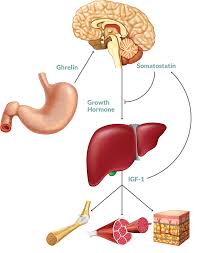

Let’s dive a bit deeper into how growth hormone impacts our height:

During childhood and adolescence:Growth hormone is released in pulses throughout the day and night. These pulses stimulate the growth of bones and cartilage, allowing us to grow taller. The amount of growth hormone released varies from person to person and is influenced by factors like genetics, nutrition, and sleep.

The theory goes like this: some believe that specific meditation practices could stimulate the pituitary gland. This gland, located at the base of the brain, plays a crucial role in the production of human growth hormone (HGH), which is essential for growth and development during childhood and adolescence.

The pituitary gland acts like a control center for various bodily functions, including growth. It releases HGH, which signals the body to produce new cells and tissues, leading to growth. HGH production peaks during childhood and adolescence, gradually declining as we age.

The pituitary gland, often called the “master gland,” is a small gland located at the base of the brain. It produces hormones that regulate various bodily functions, including growth. Growth hormone (GH), produced by the pituitary gland, is essential for growth and development during childhood and adolescence.

Think of the pituitary gland as the boss of your endocrine system. It’s a tiny gland in your brain that produces and releases essential hormones that control various bodily functions, including:

Growth hormone (GH): This is the star player when it comes to height growth. It’s vital for the development of bones and tissues, especially during childhood and adolescence.

Thyroid-stimulating hormone (TSH): This hormone controls your thyroid gland, which affects your metabolism and growth.

Adrenocorticotropic hormone (ACTH): This hormone plays a key role in regulating your body’s stress response.

Stress and the Pituitary: Chronic stress can disrupt the pituitary gland’s normal function, leading to imbalances in hormone production. Growth hormone is particularly sensitive to stress, and low levels can hinder growth.

Meditation and Stress Reduction: Meditation is known to effectively reduce stress levels. By calming your mind and body, meditation may help create a more balanced hormonal environment, potentially boosting growth hormone production.

Improved Sleep and the Pituitary: Meditation can also improve sleep quality. Growth hormone production peaks during sleep, so getting enough restful sleep is crucial for healthy growth.